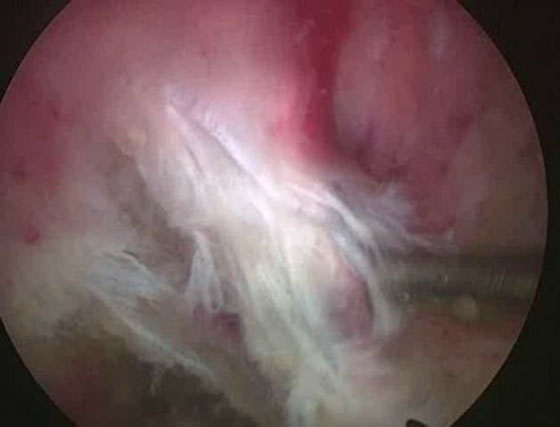

Se insufla el manguito neumático y se comienza la artroscopia por los portales anteromedial y anterolateral, se reconoce la lesión, se solucionan lesiones asociadas (meniscales, condrales, cuerpos libres) y se pasa a realizar el túnel femoral. Se localiza la hora 12 del intercóndilo, se visualiza la tróclea femoral y se ubica el sitio del túnel femoral (hora 1 rodilla derecha, hora 11 rodilla izquierda) (Fig. 2). Este túnel debe estar lo más alto posible en el intercondilo para colocar un injerto bien “vertical”. Realizamos este paso primero, haciendo el túnel desde el portal anterolateral, para evitar la dificultad de realizarlo después de la liberación capsular posterior que nos dejará menor cantidad de líquido intraarticular, y consecuentemente menor distensión dificultando la visión. Identificado el sitio de inserción, y sin resecar las fibras remanentes se coloca la fresa del diámetro a utilizar de manera de buscar que queden unos 3 mm desde la parte periférica proximal de la fresa hasta el cartílago articular del fémur, se pasa a través de la fresa canulada un clavo guía, se retira la fresa para confirmar la ubicación y se realiza el túnel de 20 o 25 mm de largo, de acuerdo al tipo de injerto que utilicemos. A continuación se ubica el espacio entre las fibras remanentes del LCP y el LCA, se debrida con shaver para dejar permeable este espacio, que nos permitirá más tarde traer el injerto desde la inserción tibial hacia la parte anterior de la rodilla (Fig. 3).

Figura 3